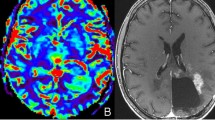

In this study, the potential of semiquantitative and quantitative analysis of dynamic contrast-enhanced (DCE) magnetic resonance imaging (MRI) was investigated to differentiate glioblastoma (GB) from radiation necrosis (RN) in rats.

F98 GB growth was seen on MRI 8–23 days post-inoculation (n = 15). RN lesions developed 6–8 months post-irradiation (n = 10). DCE-MRI was acquired using a fast low-angle shot (FLASH) sequence. Regions of interest (ROIs) encompassed peripheral contrast enhancement in GB (n = 15) and RN (n = 10) as well as central necrosis within these lesions (GB (n = 4), RN (n = 3)). Dynamic contrast-enhanced time series, obtained from the DCE-MRI data, were fitted to determine four function variables (amplitude A, offset from zero C, wash-in rate k, and wash-out rate D) as well as maximal intensity (ImaxF) and time to peak (TTPF). Secondly, maps of semiquantitative and quantitative parameters (extended Tofts model) were created using Olea Sphere (O). Semiquantitative DCE-MRI parameters included wash-inO, wash-outO, area under the curve (AUCO), maximal intensity (ImaxO), and time to peak (TTPO). Quantitative parameters included the rate constant plasma to extravascular-extracellular space (EES) (K trans), the rate constant EES to plasma (K ep), plasma volume (V p), and EES volume (V e). All (semi)quantitative parameters were compared between GB and RN using the Mann-Whitney U test. ROC analysis was performed.

Wash-in rate (k) and wash-out rate (D) were significantly higher in GB compared to RN using curve fitting (p = 0.016 and p = 0.014). TTPF and TTPO were significantly lower in GB compared to RN (p = 0.001 and p = 0.005, respectively). The highest sensitivity (87 %) and specificity (80 %) were obtained for TTPF by applying a threshold of 581 s. K trans, K ep, and V e were not significantly different between GB and RN. A trend towards higher V p values was found in GB compared to RN, indicating angiogenesis in GB (p = 0.075).

Based on our results, in a rat model of GB and RN, wash-in rate, wash-out rate, and the time to peak extracted from DCE-MRI time series data may be useful to discriminate GB from RN.